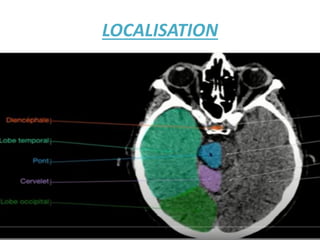

LOCALISATION

IL FAUT DETERMINER L'ÉTAGE Où VOUS ETES SUR LA TDM

POUR PRECISER LA LESION : Lésions intracrâniennes sus- et

sous-tentorielles !!

• L'intérieur du crâne est divisé en deux étages par la tente

du cervelet:

• L'étage sus-tentoriel qui contient les hémisphères

cérébraux et les structures profondes situées autour du

IIIéme ventricule.

• L'étage sous-tentoriel (que l'on pourrait aussi appeler

«fosse postérieure») qui contient le cervelet et le tronc

cérébral. Cet espace est limité supérieurement par la tente

du cervelet, inférieurement par le trou occipital et

latéralement par la boite crânienne.